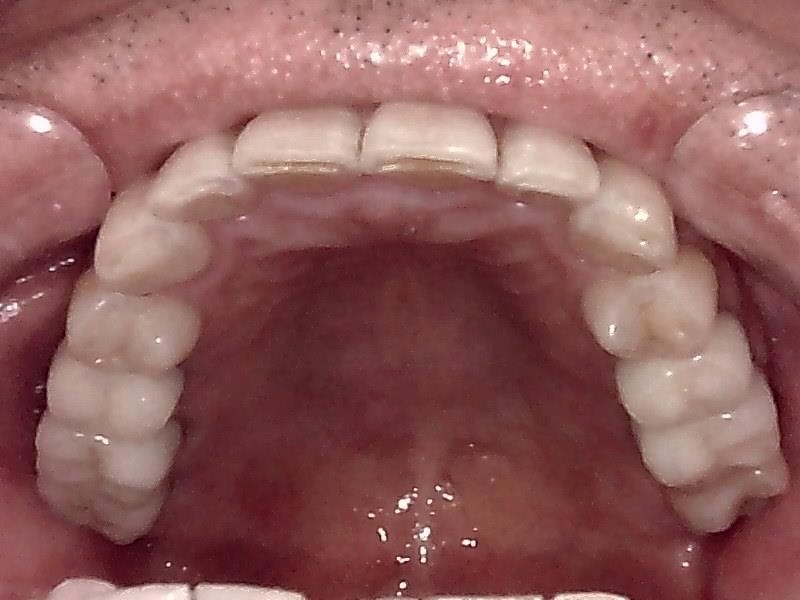

上顎